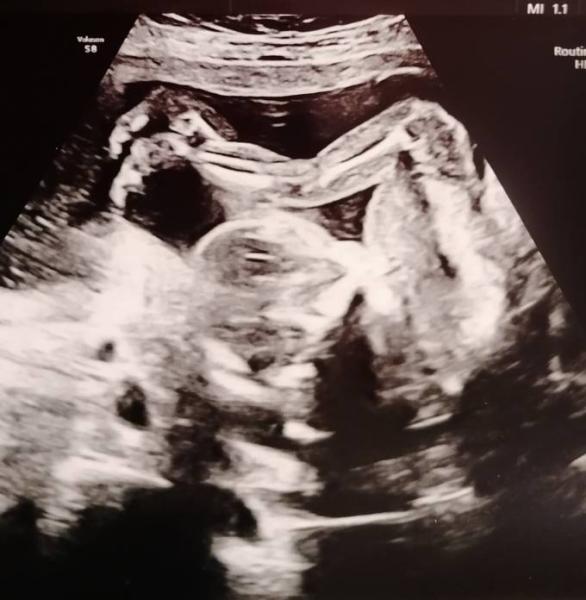

Komme grade vom FA - dem Kleinen geht es gut und wiegt ca. 200g

Es liegt ziemlich zusammengeklappt im Bauch aber trotzdem konnte mir der FA ein Geschlechtsupdate geben....

Wir sind wsl. Team rosa

- kann das aber noch immer nicht so recht glauben

, dass wir nach 1 Mädel und 3 Jungs jetzt wieder ein kleines Mädchen erwarten

Das Foto ist ein Kracher !

Und wie genau man alles sieht! Unglaublich!

Haha das bild ist ja wirklich mega

Das Bild ist wirklich der Hammer